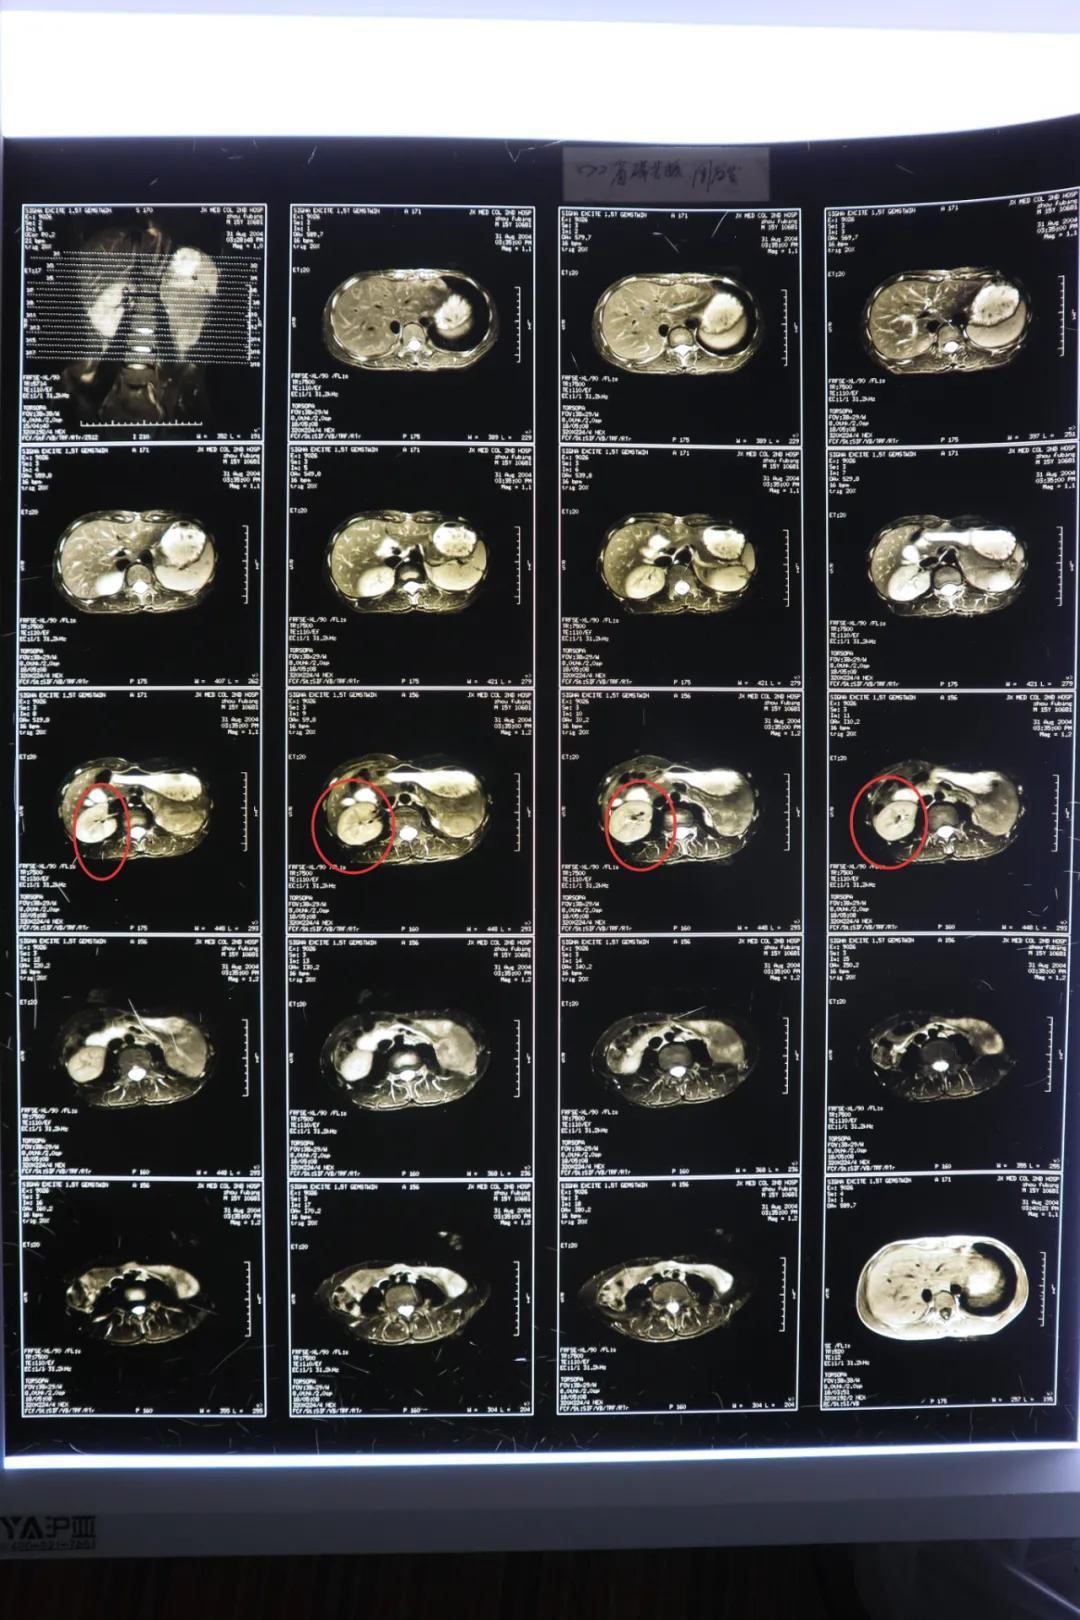

肾错构瘤破裂出血急诊手术~天门市中医医院泌尿外科

图片尺寸3022x4030